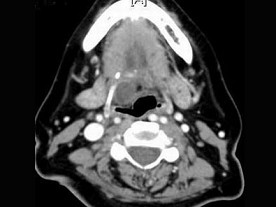

10.CT檢查結果如下,患者的最可能的診斷為  (    )

正確答案:9.A;10.C;11.D